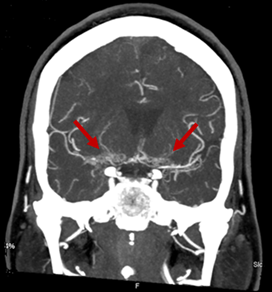

Figure 2 On axial CT angiography, evidence of collateral circulation (indicated by red arrows) and occlusion of the right M1 middle cerebral artery (indicated by a yellow arrow) can be observed.

Despite the unclear CVD, the patient remained asymptomatic until September 2019 when she was admitted for left hemiparesis with dysarthria and conjugate deviation of gaze to the right. The computed tomography (CT) angiography showed a recent right parietal ischemic infarction, occlusion of the terminal portion of the right ICA and the M1 segment of the right middle cerebral artery, and marked stenosis of the terminal portion of the left ICA, the left M1 portion, and the A1 segments of the anterior cerebral arteries, with marked collateral circulation from the lenticulostriate and thalamus-perforating arteries with occlusion of the terminal portion of the ICA, demonstrating the moyamoya pattern (Figure 1 & 2). Progressive neurological deterioration culminated in the patient's death.